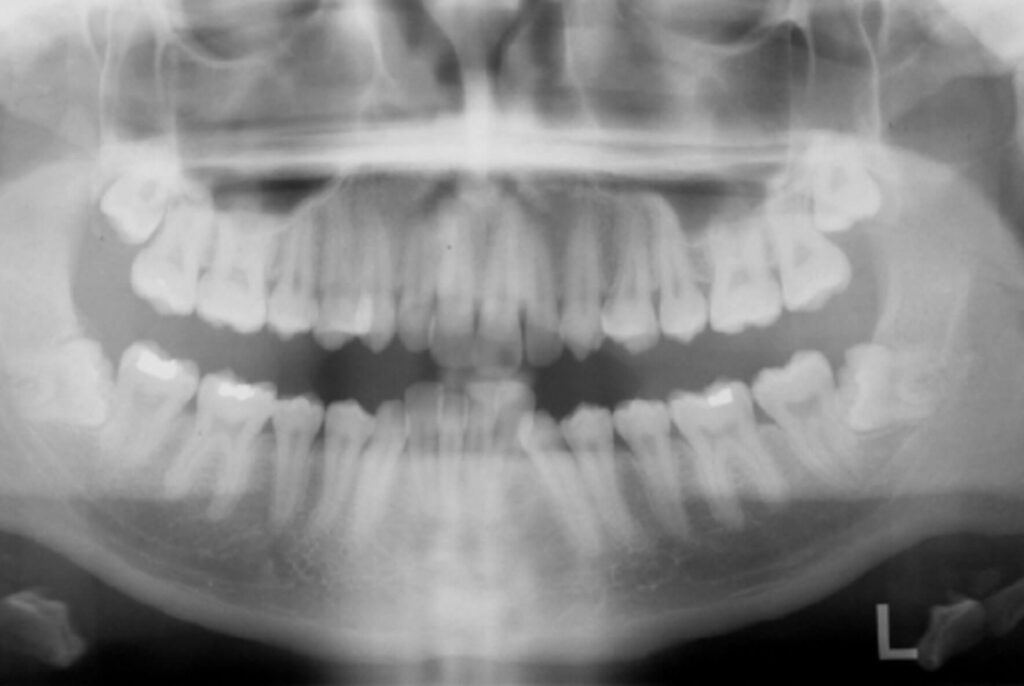

Na radiografia panorâmica foi observada a presença de angulação distal das raízes dos caninos inferiores. Foi possível notar ainda a presença dos dentes inclusos 18 (terceiro molar superior direito), 28 (terceiro molar superior esquerdo) 38 (terceiro molar inferior direito) e 48 (terceiro molar inferior direito), e as restaurações nos dentes posteriores. Não foi notada nenhuma alteração significante nas estruturas adjacentes aos dentes (Figura 3).